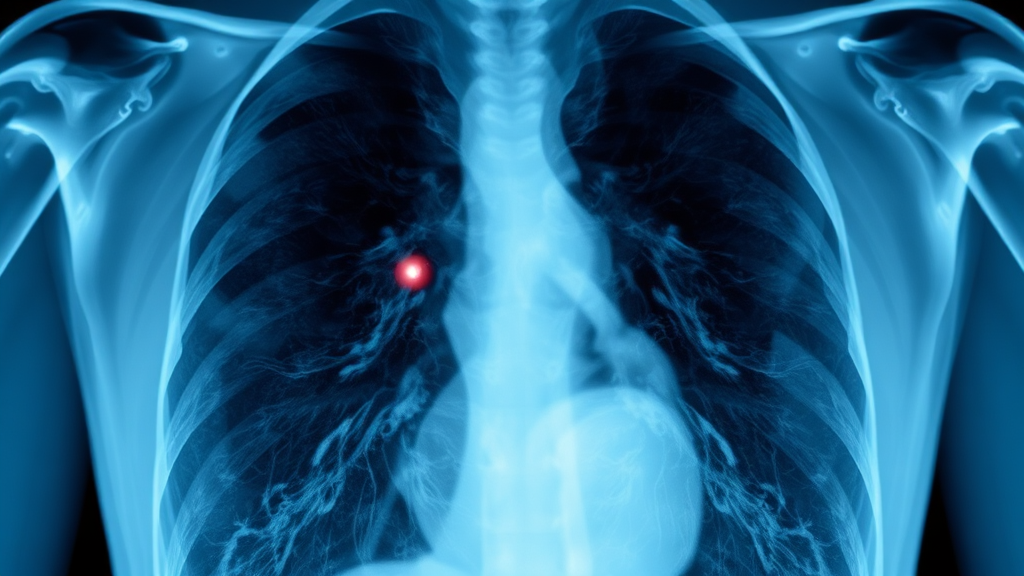

폐에 생기는 작은 혹이 바로 폐결절이에요. 건강검진 중 엑스레이나 CT 촬영에서 우연히 발견되는 경우가 많아요. 크기는 3cm 이하로 다양하답니다.

기본 검사: 흉부 X-ray

엑스레이를 통해 폐의 전체적인 모습을 확인하고, 결절 유무를 1차적으로 판단해요. 하지만 작은 결절은 놓칠 수 있어 정밀 검사가 필요할 때가 많답니다.

정밀 검사: 저선량 흉부 CT

CT는 엑스레이보다 훨씬 정밀하게 폐 단면을 보여줘요. 결절의 크기, 모양, 위치, 밀도 등을 정확하게 파악할 수 있답니다.

악성 의심 시: PET-CT 검사

암세포가 정상 세포보다 대사 활동이 활발하다는 점을 이용해 악성 여부를 판단해요. 암세포가 있는 부분은 밝게 빛나는 것처럼 보인답니다.